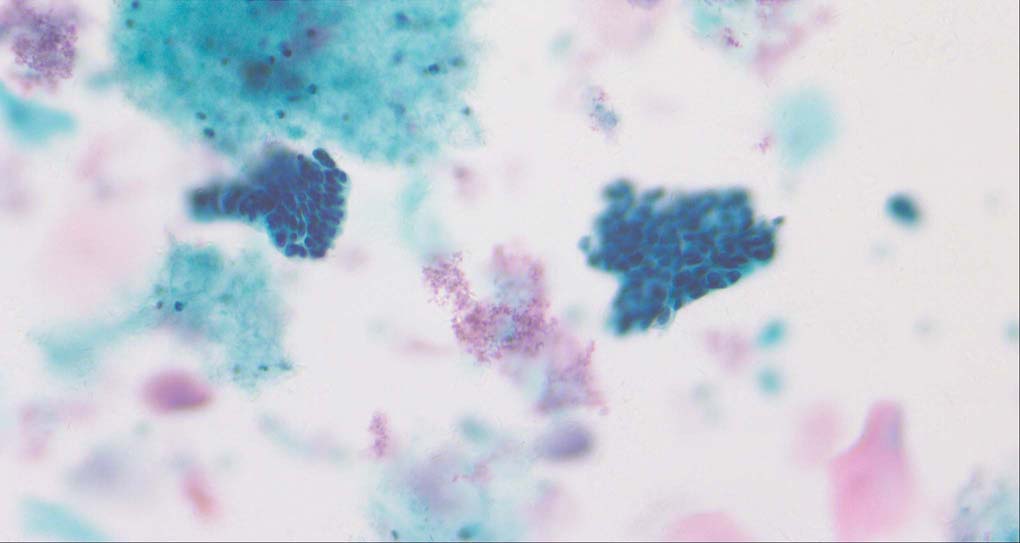

Pixel-level image fusion intends to combine different images of the same scene by mathematical techniques in order to create a single composite image that will be more comprehensive and thus, more useful for human or machine perception [1, 2]. For instance, multi-modal image fusion [3] tries to fuse images which have been acquired via different sensor modalities exhibiting diverse characteristics for a more reliable and accurate medical diagnosis. Another typical application is the multi-focus image fusion [4]. As the depth-of-field (DoF) of bright-field microscopy is only about 1~2 micrometers, while the specimen’s profile covers a much larger range and then the parts of the specimen that lie outside the object plane are blurred. The multi-focus image fusion can obtain an all-in-focus image from multiple images taken under different distance from the object to the lens of the identical view point.

A good image fusion method should contain the following properties. First, it preserves both the details of small size objects and the integrity information of large size objects in the fused image, even in the case of the size of the interested objects varying largely in the image. For example, the cervical cell images from the microscope contain both small size isolated cells and large size agglomerates, which are both useful for cervical cytology [5]. Second, it should be efficient enough to handle large-scale data. For instance, it needs to process thousands of fields of view (FoV) in an acceptable time for the whole slide scanning in digital cytopathology [6], which requires to fuse a series of high resolution images captured at each FoV in a very efficient way. Third, it does not produce obvious artifacts. Despite being studied extensively, to our best knowledge, existing fusion methods may not meet these requirements simultaneously.

To demonstrate the effectiveness and efficiency of the proposed image fusion method , we conduct a set of comparative experiments on three image datasets. The first is composed by 8 pairs of multi-modal medical images and the second one contains 15 pairs of multi-focus gray or color natural images. These two datasets are often used in many related papers and some examples are shown in Figure 3(a) and Figure 3(b). The third one is a new multi-focus cervical cell image dataset collected by ourselves, which consists of 15 groups of color images and each group contains a series of multi-focus cervix cell images with size of or , etc. Some source examples are shown in Figure 3(c). Our source code implemented in C++ along with the new multi-focus cervical cell image dataset is available online.

Figure 9, Figure 10 and Figure 11 show the comparative fused results of the multi-focus cell images shown in Figure 3(c). For clarity, we also present a closeup view in the right-bottom of each sub-picture in Figure 9 and Figure 10. As shown in the close-up views of Figure 9, the fused images based on DSIFT, IM, MWGF and BF methods are extremely blurred in the boundary and fail to keep the details of cell nucleus. Furthermore, the DTCWT and NSCT based methods produce halo artifacts in the fused images, while GFF and CNN based methods fail to preserve the small cell nucleus. LP-SR based method nearly works fine which keeps the most of the details of the small size cells, but the integrity of the clustered large size cells is damaged. Fortunately, in our proposed method, the integrity of the clustered large size cells is preserved and most of the isolated small size cells are maintained from the original images, which demonstrates the best visual quality.

Similarly, as shown in the close-up views of Figure 10, the fused images from DSIFT, IM, MWGF and BF are blurred and lose some nucleus details, while the results from DTCWT, GFF, CNN and NSCT produce halo artifacts. LP-SR based method can keep details well but also produces halo artifacts and other noise. Our method can preserve the focused areas of different source images well without introducing any artifacts. For the example illustrated in Figure 11, the fused images generated by DSIFT, DTCWT, IM and NSCT all fail to preserve the focused areas of different source images and result in extremely blurred images. The GFF, CNN, MWGF and BF based method introduces a lot of color distortion of the nucleus regions and the obvious halo artifact. The result of LP-SR based method is close to the one of our method but introduces some odd color distortion. Again, our method produces fused image which can preserve the focused areas of different source images well without introducing any artifacts.